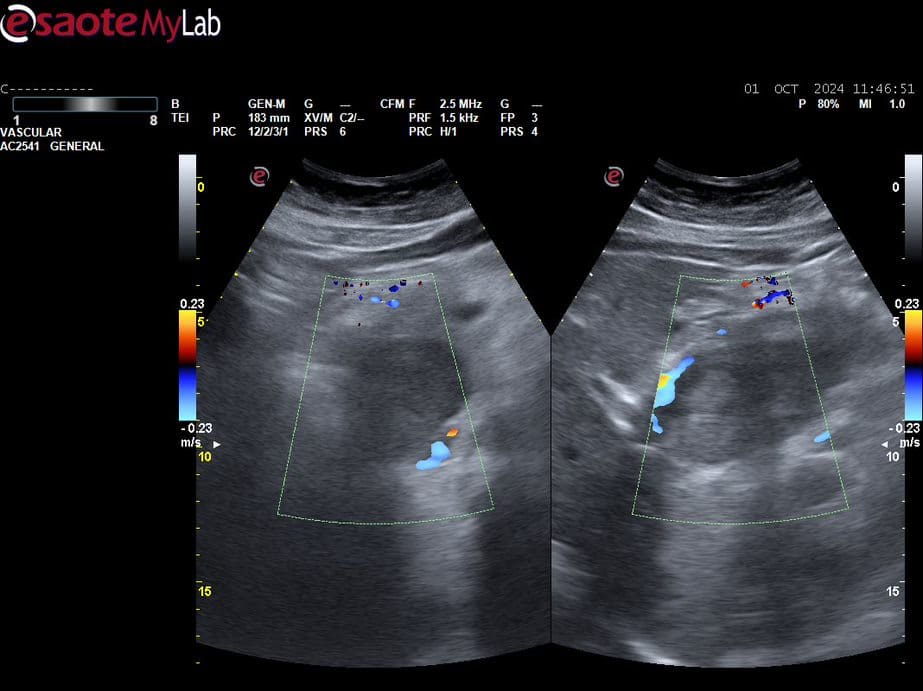

Se realiza POCUS para descartar patología vesicular, donde se halla una vesícula poco distendida sin alteraciones, además de una imagen con efecto masa de aproximadamente 2 cm en línea media, que parece depender de páncreas.

Se deriva a la paciente a urgencias con sospecha de neoplasia de páncreas, donde realizan una ecografía reglada donde se visualiza una masa sólido-necrótica de bordes imprecisos localizada en cabeza / proceso uncinado del páncreas con medidas aproximadas de 72x60x40mm, que comprime vena porta y vena cava inferior, acompañada de adenopatías retroperitoneales de aspecto patológico.